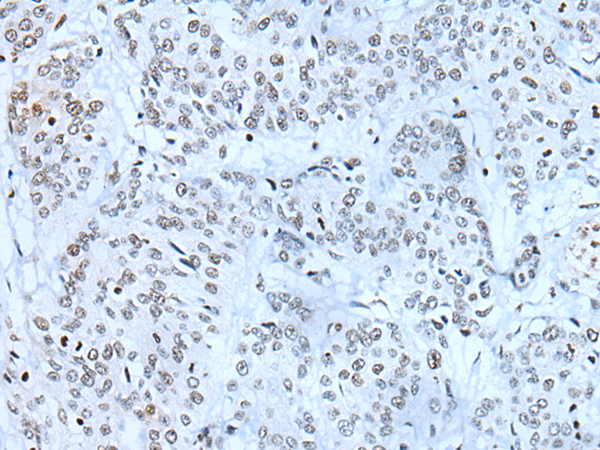

IHC positive control: